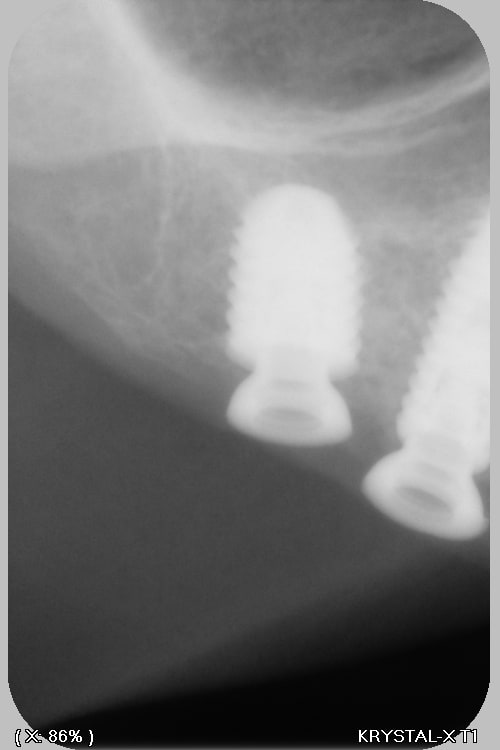

Si tu peux me donner la marque, et le type ça a été posé à Paris (2018?) Dentiste DCD, papiers perdu patiente 85 ans, adressé par un confrère qui pensait à des anthofit, mais ....

Bah, tu fatigues pxav? c'est pas des axiom reg avec ces piliers miltiunits comme ceux des TL????

Ces implants donnent le mal de mer !!! (cf pano !)

au départ je cherchais des Antogyrs , mais mon hésitation, est due au fait que (malgré mon stock de clé) je n'ai rien trouvé pour dévisser le multi unit...Bizarre, vous avez dit bizarre

C'est de l'Anthogyr avec des piliers InLink

Il faut utiliser le tournevis Anthogyr pour accès angulé (tête boule)

Effectivement, c'est le seul truc que je n'utilise pas chez eux...c'est très ingénieux, mais dans le cas présenté, ils ont tous cassés..., j'attends de voir la prothèse d'origine pour savoir d'où vient le soucis.